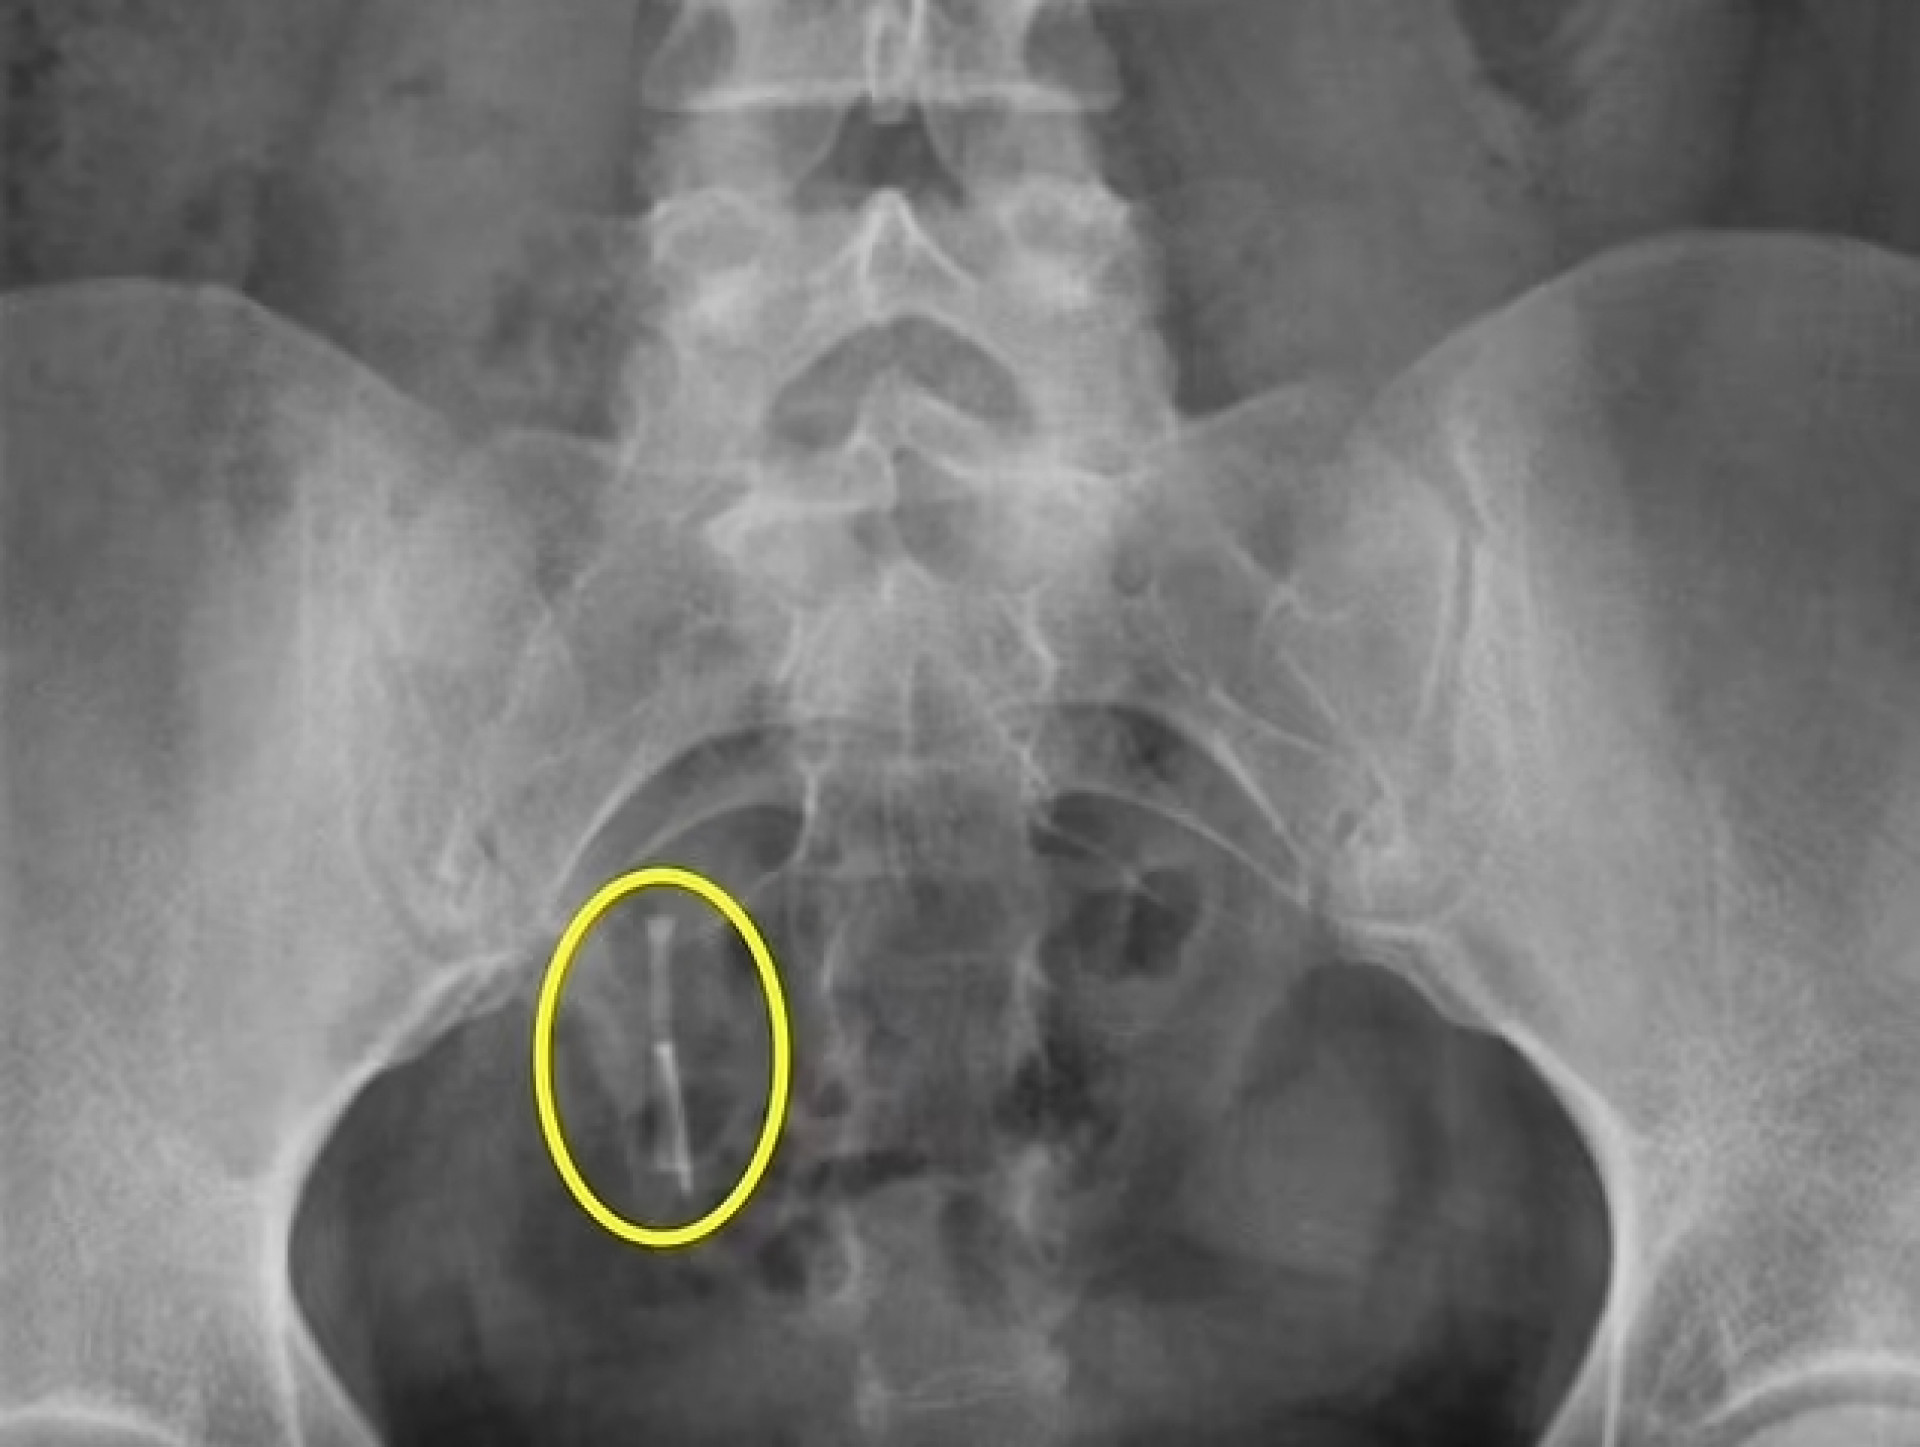

Raio-X realizado após um acidente de carro identificou o DIUReprodução / Daily Mail

Daniella Hampton, 29, encontrou, alojado no reto, um dispositivo intrauterino (DIU) que estava perdido dentro do seu corpo há 12 anos. Ele foi identificado por um raio-X feito depois que a mulher, que é dos Estados Unidos, sofreu um acidente de carro. A história foi publicada no jornal britânico "Daily Mail".

Daniella passou nove anos sem saber o que tinha acontecido com o DIU, até que ele foi encontrado na região que ela chamava atenção, em abril de 2021, após raio-X exigido por causa de um acidente de carro. Ele estava no cólon dela e migrou para lá depois de perfurar o útero. Uma cirurgia foi feita para retirá-lo cinco meses depois.